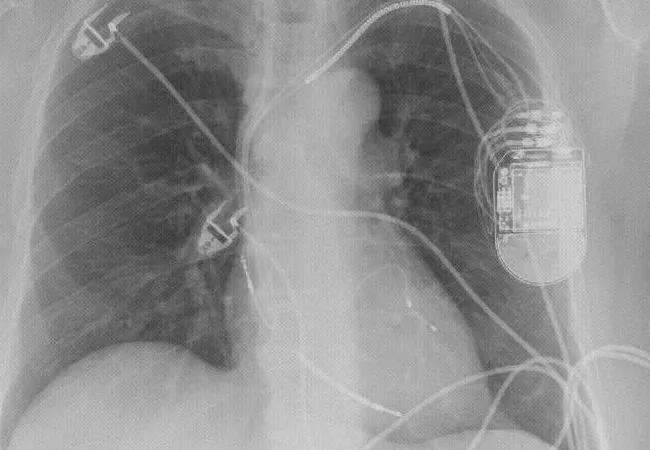

A pre-CRT electrocardiogram from the type of patient found to potentially benefit from CRT in the new analysis — a 56-year-old woman with nonischemic cardiomyopathy, NYHA class III heart failure, QRS duration of 122 ms and an LVEF of 30 percent. The image at the top of this post is a post-CRT radiograph from the same patient showing functional recovery with ventricular remodeling (LVEF of 58 percent).